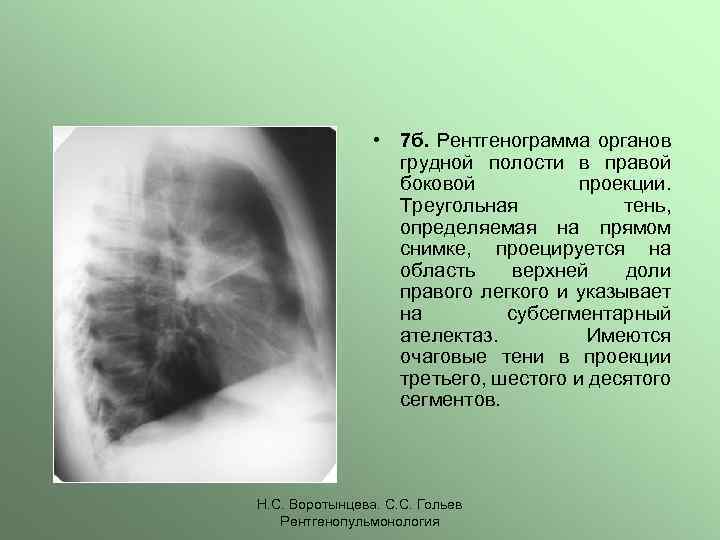

Что такое малоконтрастная рентгенограмма органов грудной клетки